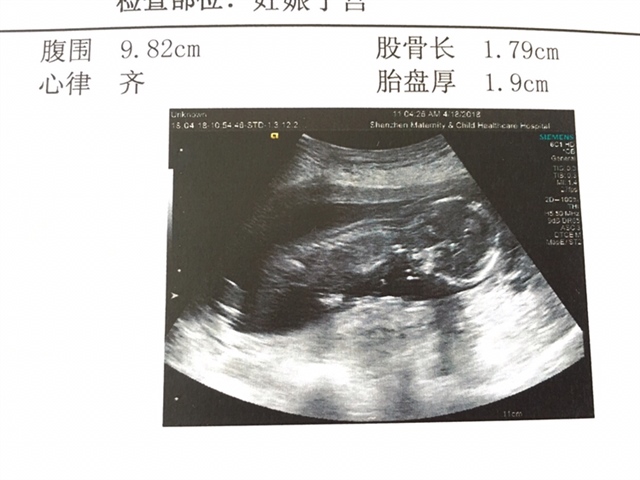

孕31周+6天